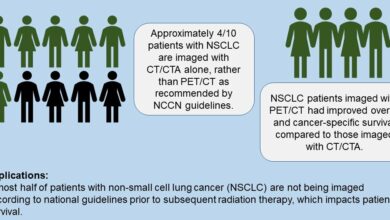

Muitos pacientes do Medicare com câncer de pulmão de células não pequenas não foram classificados de acordo com as diretrizes, levando a taxas de mortalidade mais altas

Resumo dos achados de imagem do banco de dados vinculado ao SEER-Medicare para pacientes com câncer de pulmão de células…